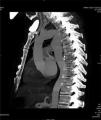

Case reportA 54-year-old man arrived at the hospital with symptoms of abrupt chest pain radiating to the neck, not relieved by nitrates. The patient had a history of ARSA diagnosed in another hospital, with dysphagia of unknown duration. Due to the symptoms of acute aortic syndrome, CTA was performed (Figure 1), findings of which were compatible with a dissecting aneurysm of an ARSA compressing the esophagus. The origin of the left subclavian, left carotid and right carotid arteries were not dissected, nor were the ascending thoracic aorta or the descending thoracic aorta. The maximum diameter of the ascending thoracic aorta was 39 mm. Subsequently, aortography (Figure 1) visualized a bulbous origin of the right subclavian artery, diagnostic of KD. Placement of an endoprosthesis at the outlet of the ARSA was ruled out on technical grounds due to the lack of an anchoring zone between the two subclavian arteries. Echocardiography showed a bicuspid aortic valve without flow alterations, aortic root and ascending aorta of normal size, and both ventricles of normal size and contractility.

The patient's postoperative course was favorable with hemodynamic stability and early extubation. There were no clinical or Doppler signs of critical ischemia in either upper extremity. Postoperative CTA (Figure 2) revealed no sign of complications in the thoracic aorta replacement. Both the right subclavian and the internal thoracic artery were perfused by the vertebral artery through the thoracic inlet. Postoperative echocardiography showed the bicuspid aortic valve to be free of flow alterations, and biventricular function remained good.